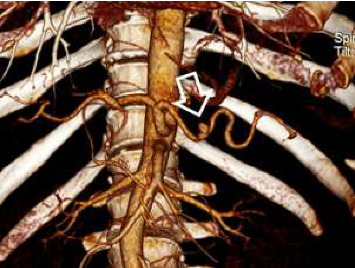

Hemosuccus pancreaticus (HP) is a rare but potentially life-threatening condition, characterized by upper gastrointestinal bleeding from the ampulla of Vater, often originating from a ruptured pseudoaneurysm of the peripancreatic arteries. Despite its rarity, HP presents a diagnostic and therapeutic challenge due to its elusive clinical presentation and complex underlying pathophysiology. In this case report, we presented a compelling instance of HP, diagnosed in a 48-year-old man, complicated with gastrointestinal bleeding and severe anemia successfully managed with urgent endovascular intervention. We highlighted the importance of early recognition, prompt intervention, and interdisciplinary collaboration in achieving favorable outcomes in patients afflicted by this distinctly unusual condition.